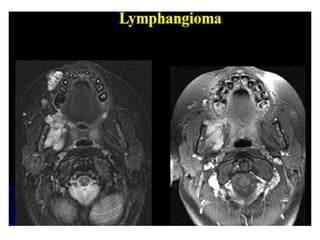

O documento fornece informações sobre como realizar exames de ressonância magnética do pescoço e angiorressonância magnética das carótidas, incluindo parâmetros, programação, anatomia, exames estruturais e funcionais, dicas e protocolos.